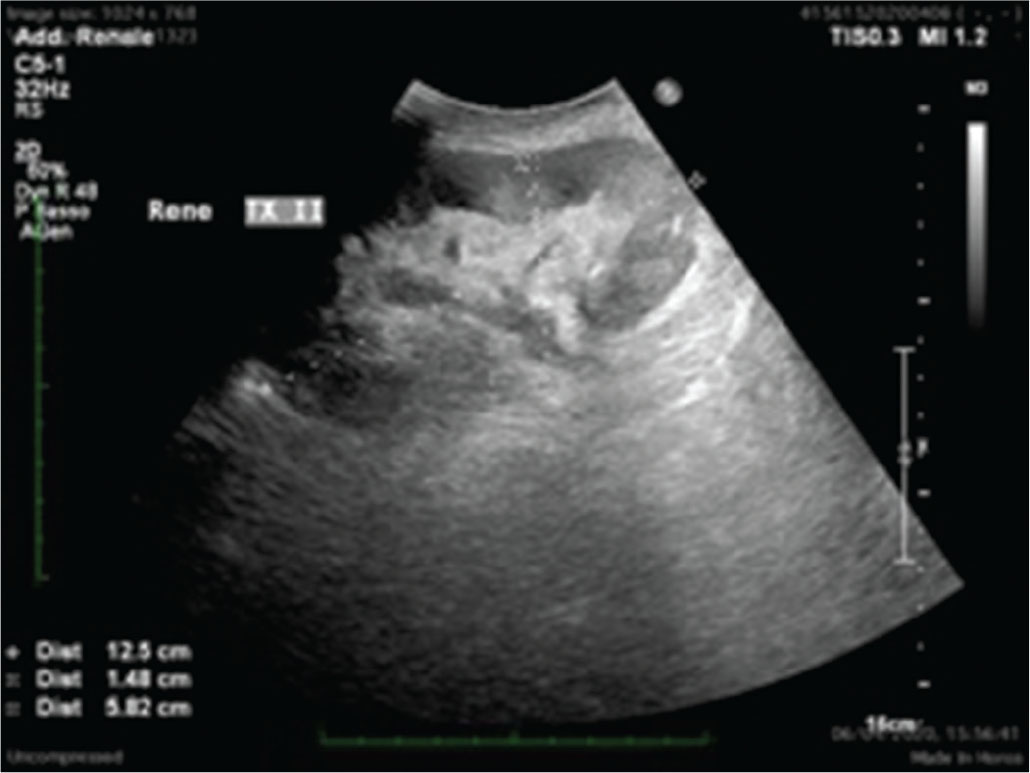

Dal punto di vista morfostrutturale, il rene trapiantato appare molto simile a quello nativo, anche se l’assenza della capsula adiposa perirenale e la sua posizione molto superficiale potrebbero modificarne leggermente le caratteristiche ecogeniche (Fig. 1).

Anche le sue dimensioni sono simili a quelle dei reni nativi, anche se, progressivamente, tendono a incrementarsi per i processi di iperfiltrazione. Il parenchima renale e la differenziazione cortico-midollare sono solitamente ben visibili e caratterizzabili. Il sistema collettore di un TR ben funzionante può apparire lievemente dilatato, anche in relazione alla presenza dello stent ureterale JJ, ben visibile ecograficamente grazie alla sua immagine a doppio binario lineare che termina, da una parte, nella pelvi renale e, dall’altra, in vescica. In aggiunta, l’elevata quantità di urina che scorre nelle vie urinarie principali e la perdita di tonicità ureterale derivata dalla sua denervazione sono fattori potenzialmente favorenti lo sviluppo di idronefrosi moderata.

(Personal image, Fondazione IRCCS Ca’ Granda Ospedale Maggiore Policlinico, Milano)